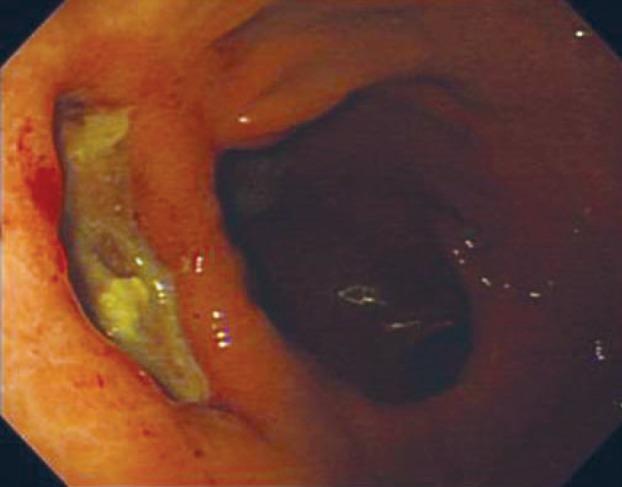

A gastropericardial fistula, defined as penetration of a gastric lesion into the pericardium, is a rare occurrence. Such a fistula is usually associated with a huge ulcer in the gastric fundus, an ulcer within a hiatus hernia, a history of esophagogastric surgery, the concurrent use of non-steroidal anti-inflammatory drugs (NSAIDs), or Zollinger-Ellison syndrome. The patient in this case presented with shoulder pain and melena, caused by a gastropericardial fistula that had occurred as a late complication of postoperative esophagogastrostomy and a refractory gastric ulcer. Despite the severity of the condition, the patient showed great improvement after medical treatment and the fistula was cured at the end.

胃-心包瘘是指胃病变穿透至心包,较为罕见。这种瘘通常与胃底部的巨大溃疡、裂孔疝内的溃疡、食管胃手术史、同时使用非甾体抗炎药(NSAIDs)或卓-艾综合征有关。本例患者表现为肩痛和黑便,由胃-心包瘘引起,这是术后食管胃吻合口和难治性胃溃疡的晚期并发症。尽管病情严重,但患者经药物治疗后有了很大改善,瘘最终得以治愈。